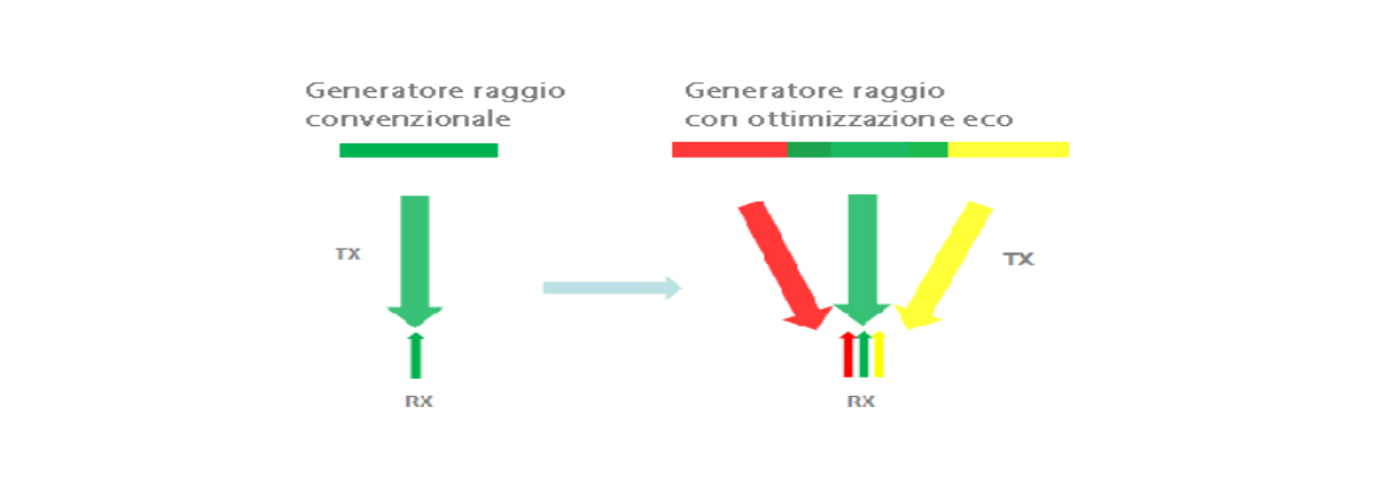

Generazione fascio con ottimizzazione eco

Il generatore del fascio con ottimizzazione eco, consente l'utilizzo di segnali di eco dei fasci adiacenti tradizionalmente trascurati per formare un fascio di imaging e pi├╣ raffinato e potente, fornendo una migliore risoluzione delle immagini ŌĆ£fuori fuocoŌĆØ ed una maggiore penetrazione dellŌĆÖimmagine.